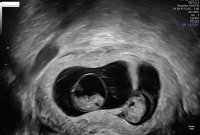

Så tristFikk se et hjerte som slo i dag, så da klarte det andre seg desverre ikke. Var litt som forventet, men allikevel trist. Men det andre målte akkurat som det skulle8+0 i dag, målt til 8+3

Fikk se et hjerte som slo i dag, så da klarte det andre seg desverre ikke. Var litt som forventet, men allikevel trist. Men det andre målte akkurat som det skulle8+0 i dag, målt til 8+3

Jeg var på første ul 8 dager før, da målte den ene 4 og den andre 7 mm. Så selvom vi fikk se to hjerter som slo så var gyn litt usikker hvordan det ville utvikle seg. Men tross alt, et bankende hjerte var helt fantastiskSå tristHvorfor var det forventet om jeg får spør?